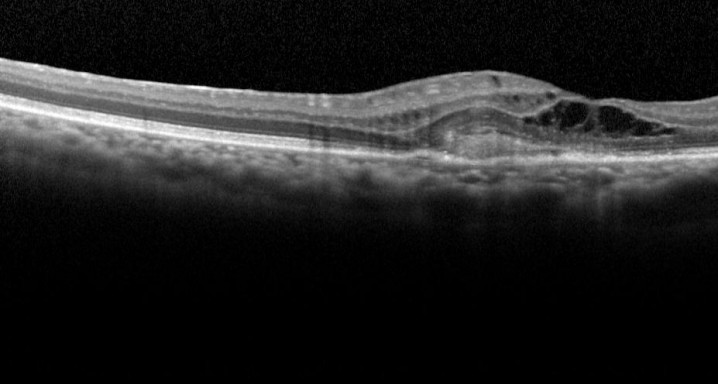

Este es un Ensayo Clínico fase III, multicéntrico, aleatorizado, con doble enmascaramiento, de dos grupos paralelos que evalúa la eficacia y la seguridad de faricimab administrado a través de inyecciones intravítreas en pacientes con degeneración macular asociada a la edad (DMAE) forma exudativa en comparación con el tratamiento con aflibercept (EYLEA®).

Pacientes mayores de 50 años con degeneración macular asociada a la edad exudativa que no hayan recibido tratamiento por esta enfermedad en el ojo de estudio.

Faricimab es el primer anticuerpo monoclonal biespecific diseñado por uso intravítreo que combina la acción antiangiogénica de los fármacos que se utilizan actualmente para el tratamiento de la DMAE con la acción antinflamatoria, neutralizando a la vez el VEGF y el angiopoietina-2 . Los resultados en estudios previos apoyan al inicio de un ensayo fase III para evaluar la eficacia y la seguridad de faricimab en el tratamiento de pacientes con DMAE neovascular, con el objetivo de aumentar los intervalos entre tratamientos.

Inyecciones intravítreasDMAE exudativa o húmeda